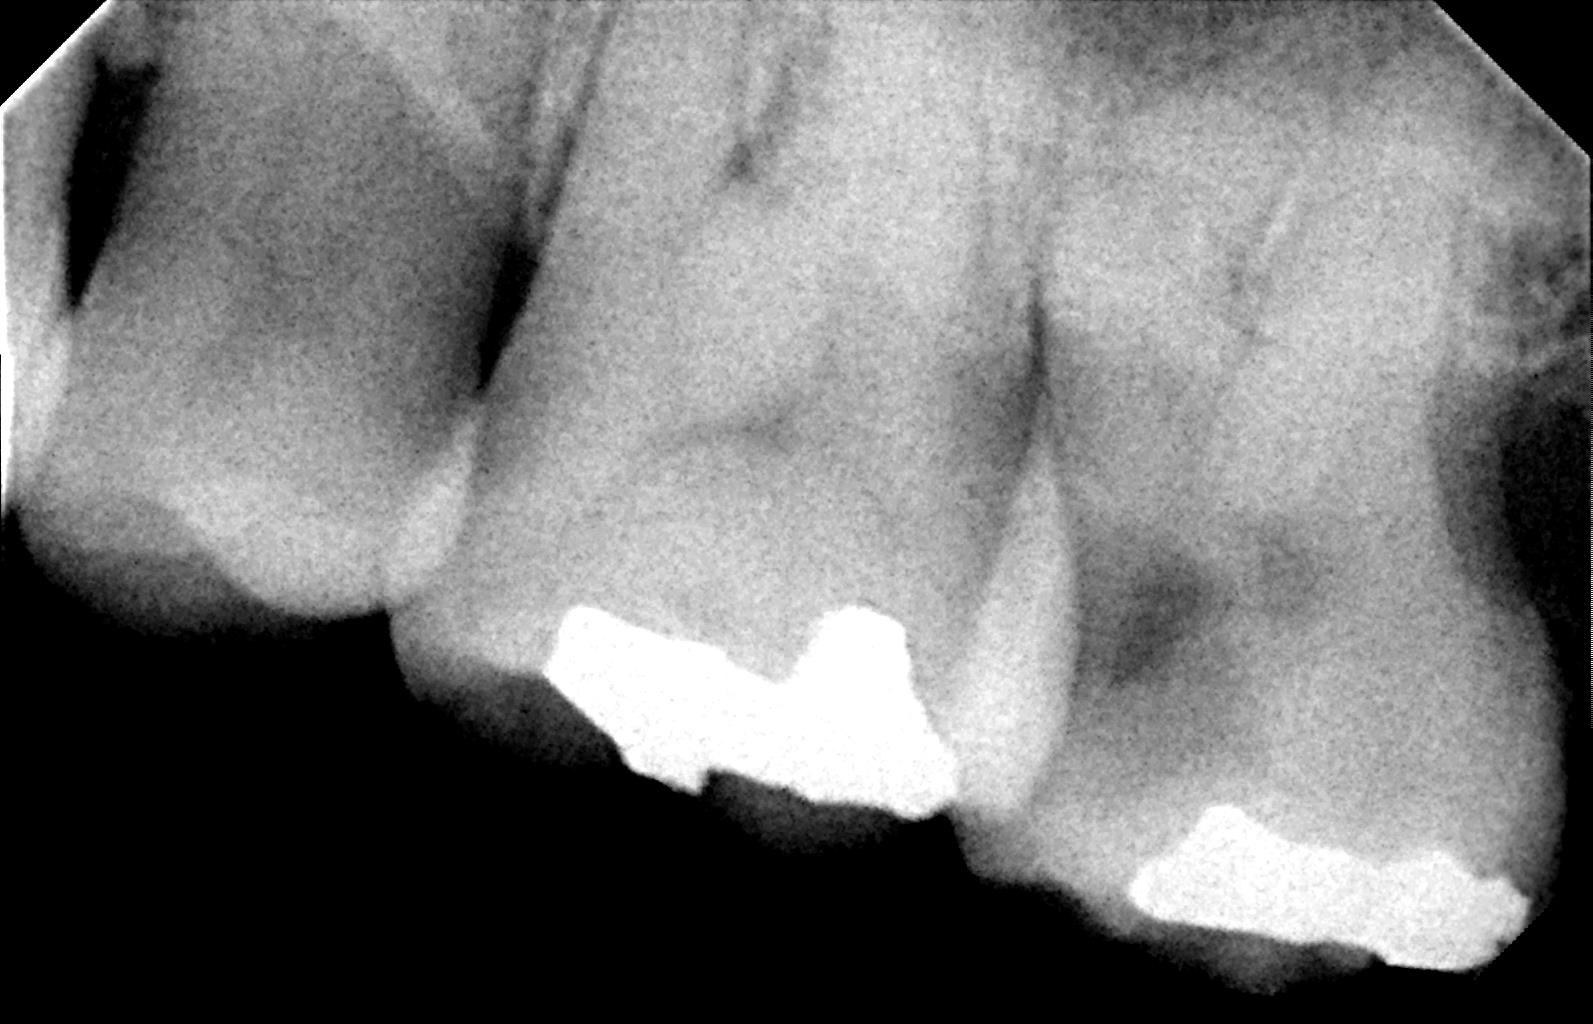

下顎右側第一大臼歯難治性根尖生歯周炎を伴った4根管症例

患者さまは他院で根の治療を受けておられたが痛みがひかず、転医されてきました。

近心根の根尖に根尖病巣があり、丹念に根管を清掃拡大し、症状が治まったところで根管充填を行いました。